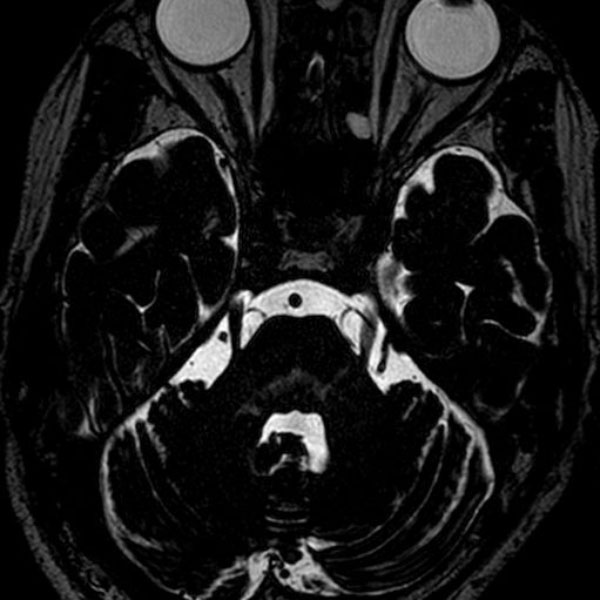

手術前

(MR1)